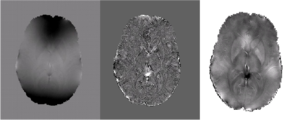

Future work will focus on quantifying magnetic susceptibility and iron content in the brain. Preliminary results based in part on the method described above are shown below in Fig 5.